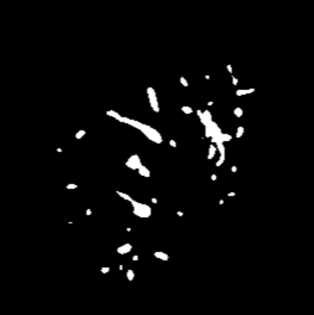

Manually segmenting the hepatic vessels from Computer Tomography (CT) is far more expertise-demanding and laborious than other structures due to the low-contrast and complex morphology of vessels, resulting in the extreme lack of high-quality labeled data. Without sufficient high-quality annotations, the usual data-driven learning-based approaches struggle with deficient training. On the other hand, directly introducing additional data with low-quality annotations may confuse the network, leading to undesirable performance degradation. To address this issue, we propose a novel mean-teacher-assisted confident learning framework to robustly exploit the noisy labeled data for the challenging hepatic vessel segmentation task. Specifically, with the adapted confident learning assisted by a third party, i.e., the weight-averaged teacher model, the noisy labels in the additional low-quality dataset can be transformed from "encumbrance" to "treasure" via progressive pixel-wise soft-correction, thus providing productive guidance. Extensive experiments using two public datasets demonstrate the superiority of the proposed framework as well as the effectiveness of each component.

翻译:将来自计算机地形学(CT)的肝脏船只人工分割,由于船只的低调和复杂形态,由于低调和复杂的形态,造成极端缺乏高质量的标签数据,因此比其他结构更需要专门知识和难度大得多。如果没有足够的高质量的说明,通常的数据驱动的基于学习的方法就会与不足的培训斗争。另一方面,直接引进低质量说明的额外数据可能会混淆网络,导致不良的性能退化。为了解决这一问题,我们提议建立一个新的、由教师协助的、有说服力的、有说服力的学习框架,为具有挑战性的肝脏船只分解任务强有力地利用响亮的标签数据。具体地说,在第三方(即加权平均教师模式)的协助下,经过变通的自信学习后,额外低质量数据集中的噪音标签可以从“阻力”转变为“压力”,通过渐进式的像素方法的软校正,从而提供富有成效的指导。使用两个公共数据集进行的广泛实验,显示了拟议框架的优越性以及每个组成部分的效能。